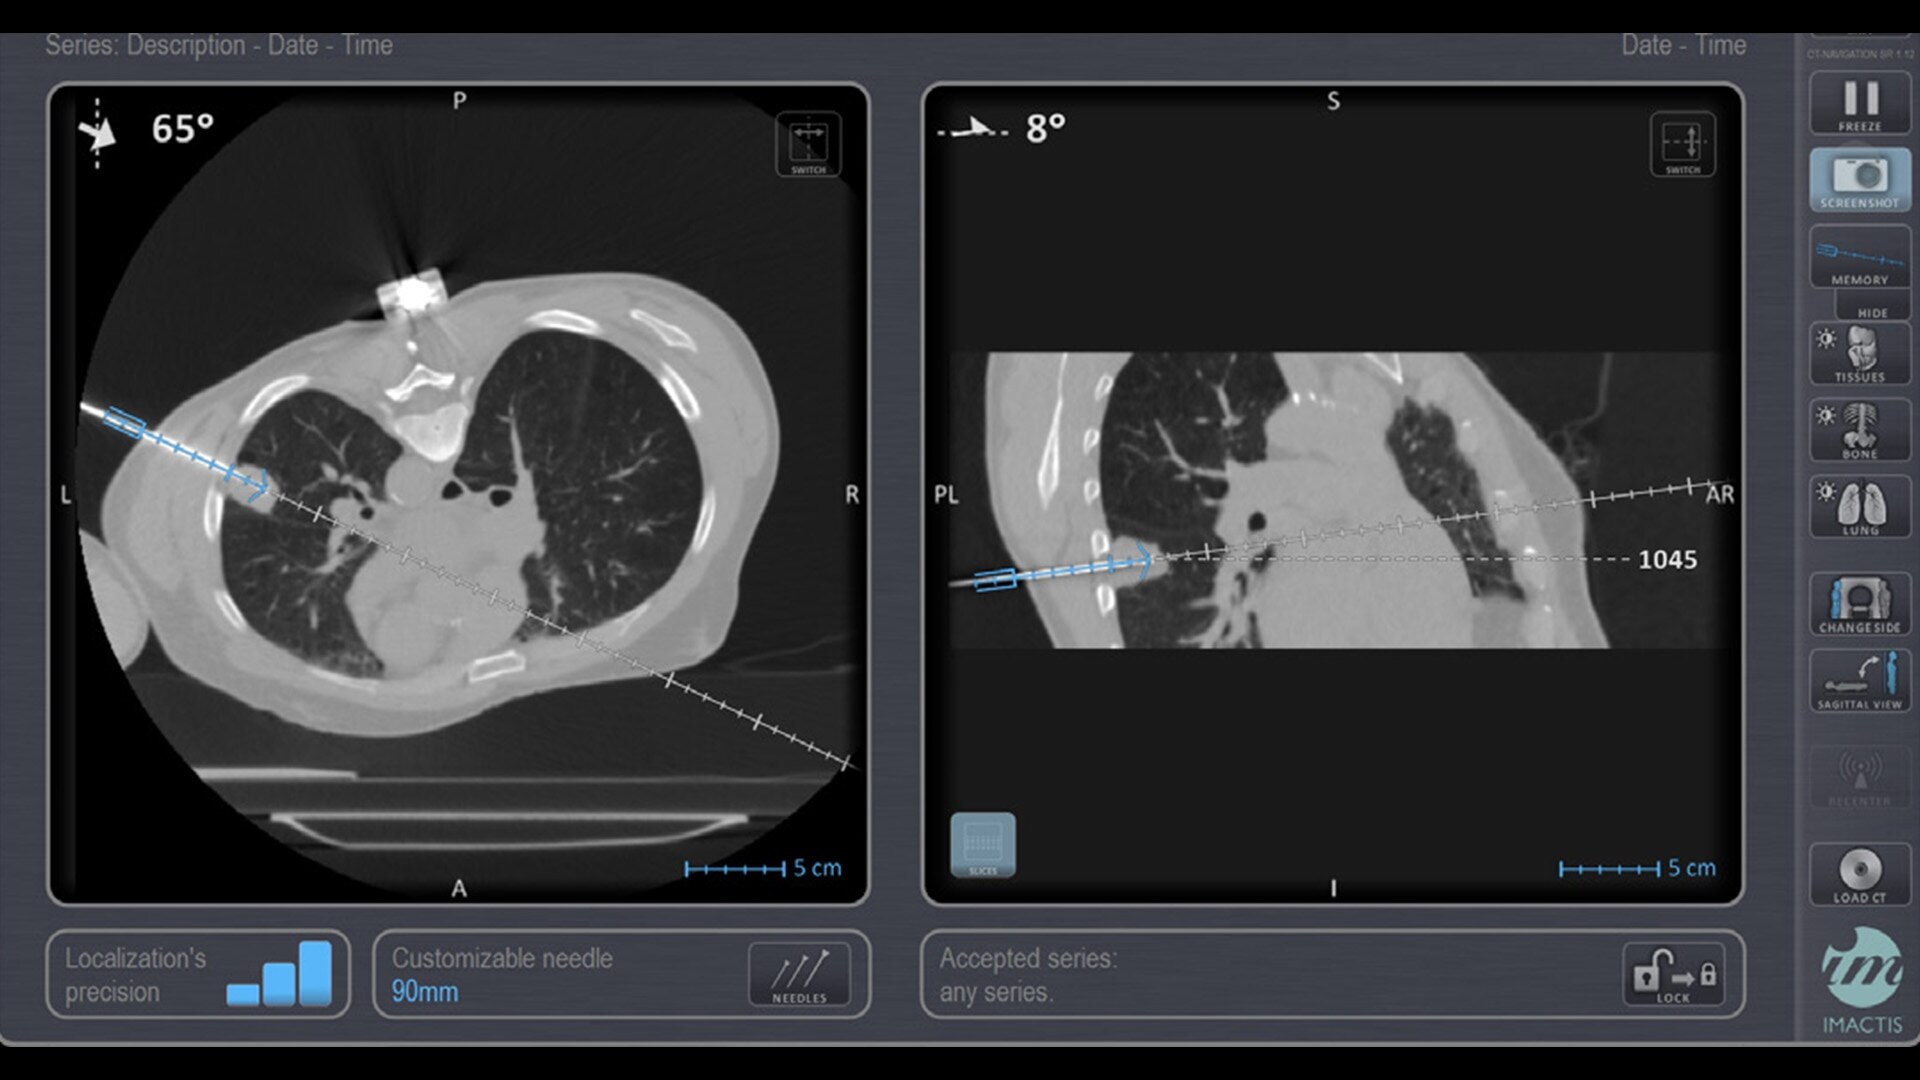

Imactis® CT-Navigation™

Planning and navigation solution for interventional percutaneous radiology that can increase procedure accuracy, reduce time, simplify workflow and reduce dose.¹

In interventional radiology, the success of the percutaneous procedure depends on correct needle positioning. The Imactis system helps the radiologist place one or more needles with great accuracy, in less time and with fewer control scans.

Imactis enables you to find the ideal path to the target.

With real-time image reconstruction, live interactive navigation and no limit in angulation, the optimal clinical choices are clear.

Live 3D needle tracking, precise reproduction of your planned trajectory and continuous needle depth measurement help ensure optimal needle placement.